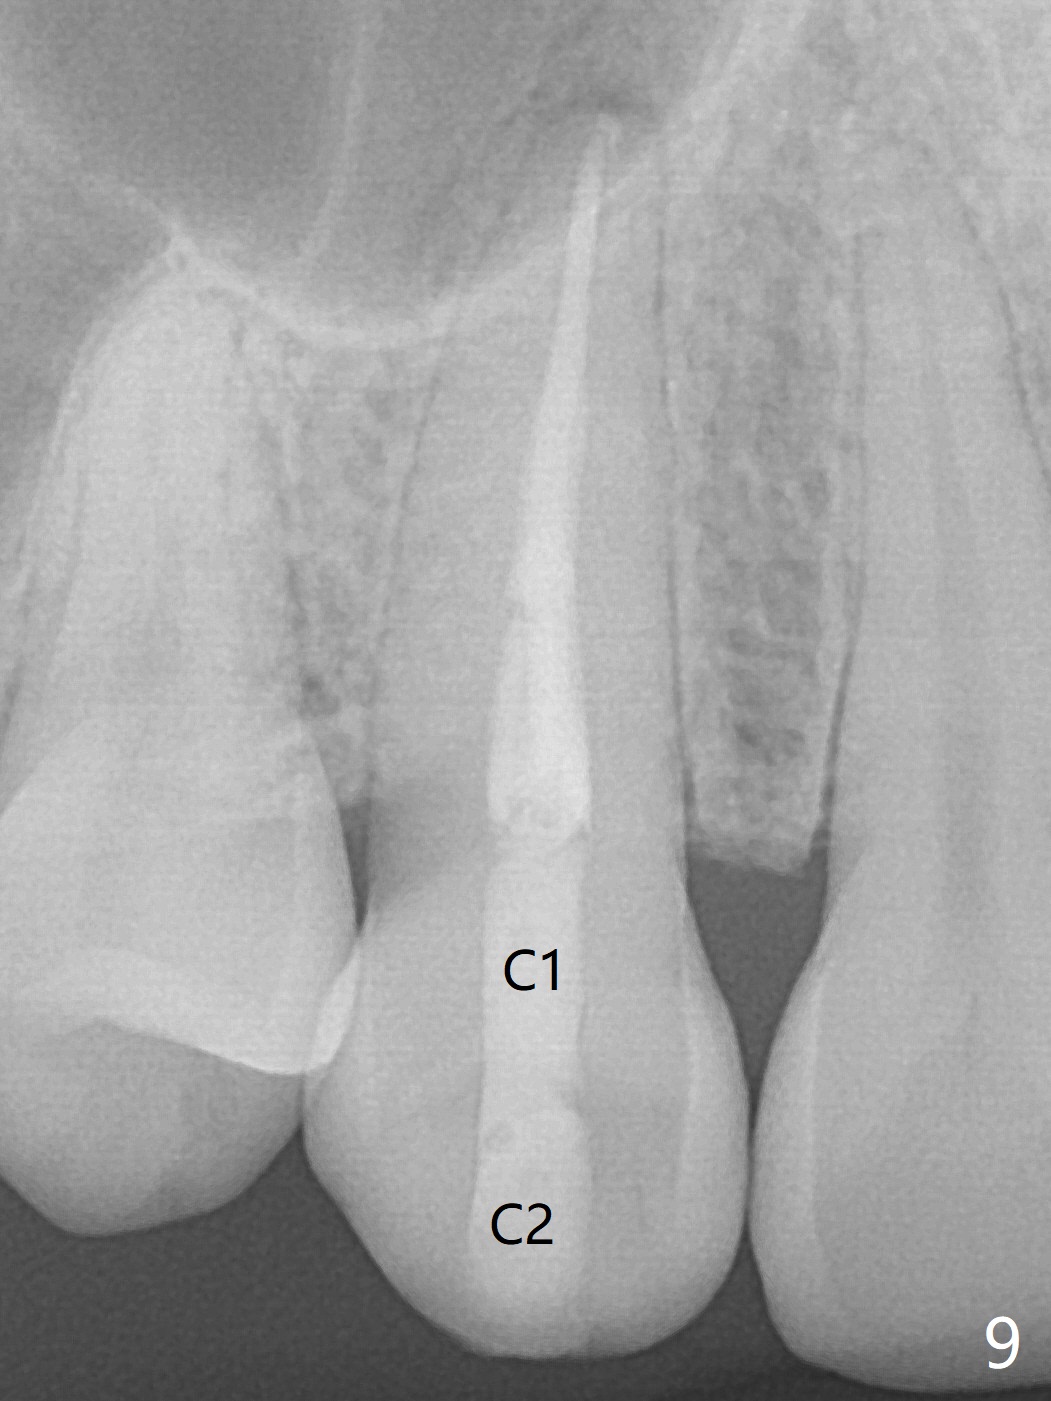

A 36-year-old woman (after #3 immediate implant and #31 socket preservation) wants to take care of the discolored canine 20 years post orthodontic treatment with extraction (Fig.1-3). RCT (Fig.4) appears to whiten the tooth (Fig.5 (A4)). The darkness appears to rebound 1 month post RCT, after removal of Gutta Percha for take home internal and external bleaching (Fig.6). The patient returns for composite after 3-week whitening (Fig.7,8). The shades of composite are bleach (flowable, C1) and B1 (packable, C2, Fig.9). The shade of the RCT tooth is compatible with that of the neighboring teeth 4 months post composite (Fig.10) when the implant at #3 has a new abutment.